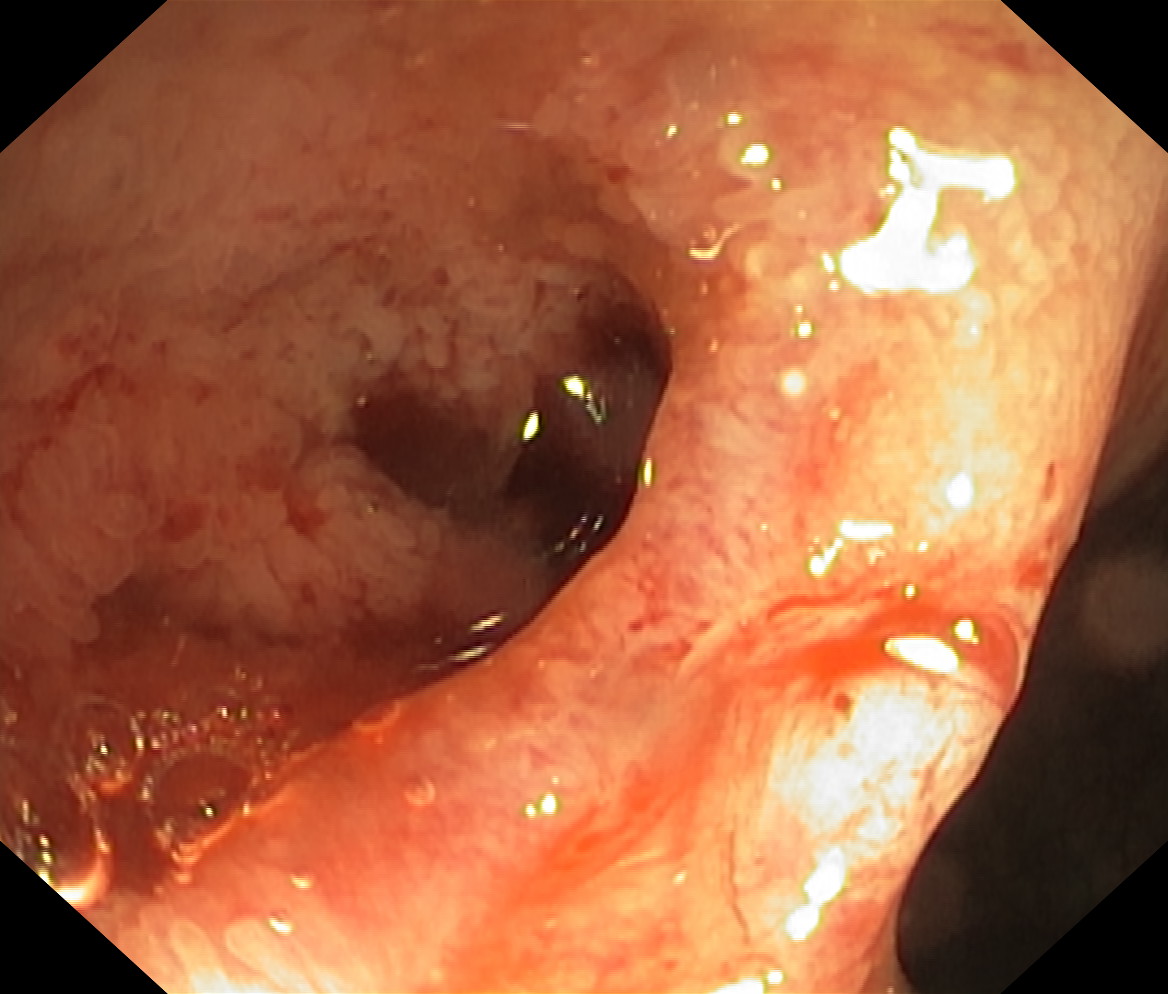

Choroba Leśniowskiego-Crohna